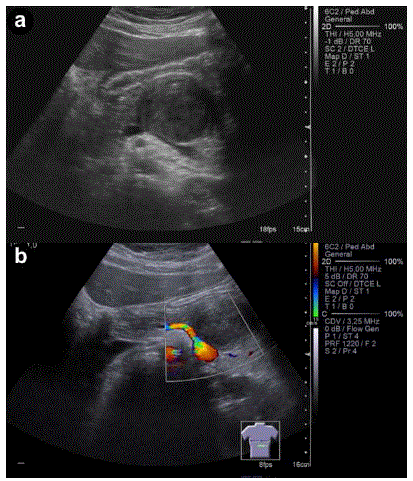

Figure 1. a. Transverse upper abdominal ultrasonography: hypoechoic heterogeneous mass of the pancreas. b. Doppler ultrasonography showing no apparent tumoral vascularization.